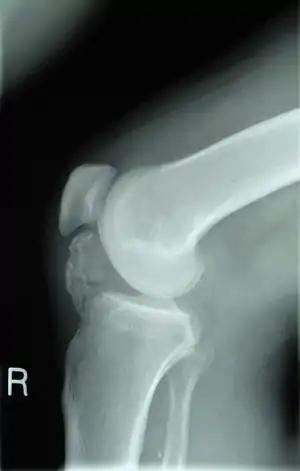

Остеохондрома

Остеохондрома — доброякісна пухлина, за зовнішнім виглядом подібна до остеоми, де чітко обмежені ділянки просвітлення чергуються з зонами затемнення та вкрапленнями вапна, також, як і хондроми, частіше візуалізуються у гайморових пазухах. Також висока ймовірність малігнізації, симптоми якої наведені вище.

![]() Остеохондрома, рентгенівський знімок Остеохондрома, рентгенівський знімок | |